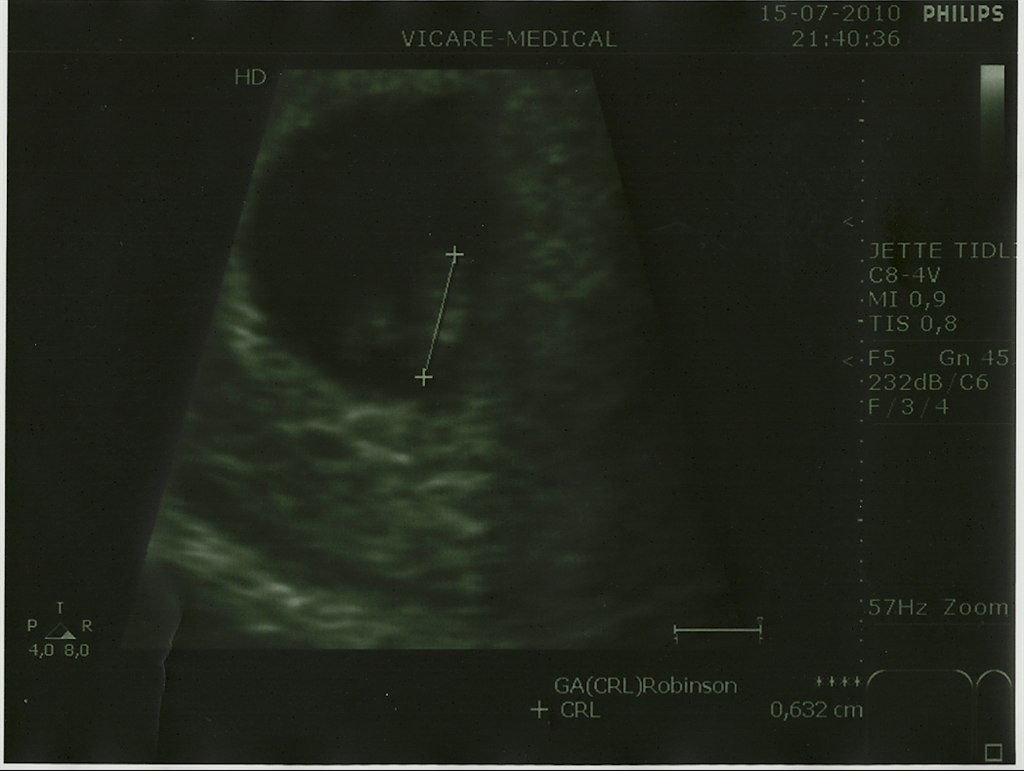

Billede 1 - 6+6